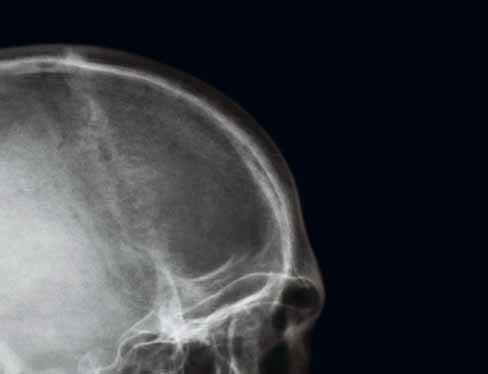

1 sutura sagittalis (šev šípový)

2 foveolae granulares

3 sutura lambdoidea (šev lambdový)

4 sinus frontalis (dutina kosti čelní)

5 strop orbity (očnice)

6 planum sphenoidale

7 cellulae ethmoidales (etmoidální sklípky / dutinky kosti čichové)

8 sutura frontozygomatica (šev mezi kostí čelní a kostí lícní)

9 horní hrana pyramidy (kosti skalní)

10 linea innominata

11 meatus acusticus internus (vnitřní zvukovod)

12 arcus zygomaticus (jařmový oblouk)

13 caput mandibulae (hlavice dolní čelisti)

14 septum nasi et concha nasalis inferior (nosní přepážka a dolní nosní skořepa)

15 sinus maxillaris (dutina horní čelisti)

16 processus mastoideus (bradavkový výběžek)

17 squama occipitalis (šupina kosti týlní)

18 dens axis (zub čepovce)

19 maxilla (horní čelist)

20 canalis mandibulae (kanál v dolní čelisti)

21 angulus mandibulae (úhel dolní čelisti)

22 mandibula (dolní čelist)

23 protuberantia mentalis (bradový výběžek)

os frontale (kost čelní)

os occipitale (kost týlní)

os temporale (kost spánková)

os zygomaticum (kost lícní)

os parietale (kost temenní)

os sphenoidale (kost klínová)